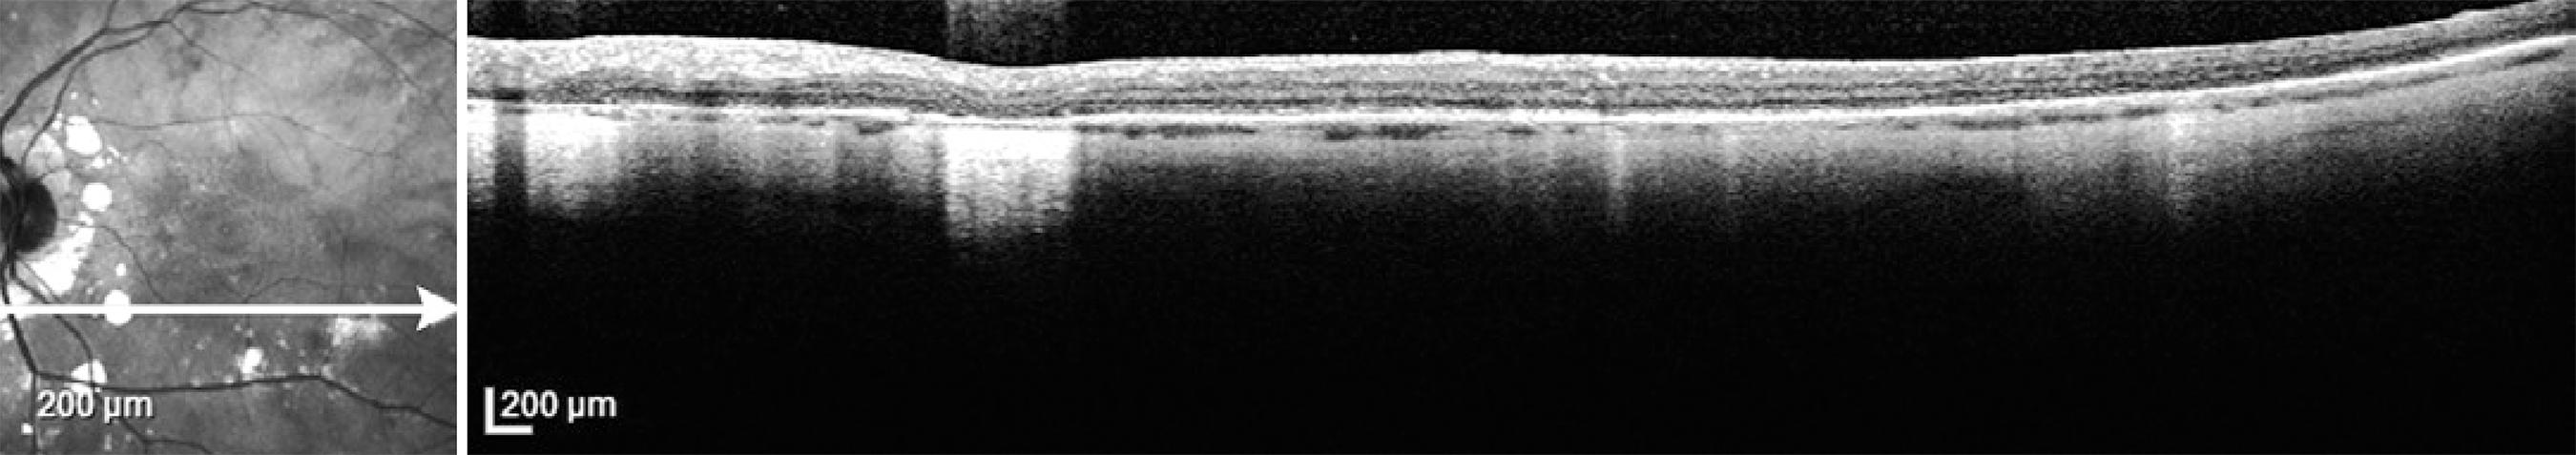

Ocular coherence tomography is an appropriate measure not only to diagnose macular edema, but also to depict macular thinning or atrophy correlating with abnormal visual function( 71 , 73 ). As the disease progresses, thinning of the choroidal vascular layer and atrophy of the outer retina will ensue. In addition, restoration of retinal physical structure is not an uncommon finding when the correct immunosuppressants are used( 64 ). Unlike other investigations, such as FA, ERG, and SITA-SWAP VF testing, it is not necessary to obtain OCT every 6 months. Rather, macular OCT is recommended when CME or macular atrophy are suspected (Figure 4).

Figure 4 Optical coherence tomography of the left eye showing localized areas of retinal pigment epithelium atrophy (BSRC lesions) and thinning of the choroid in a patient with birdshot retinochoroidopathy.